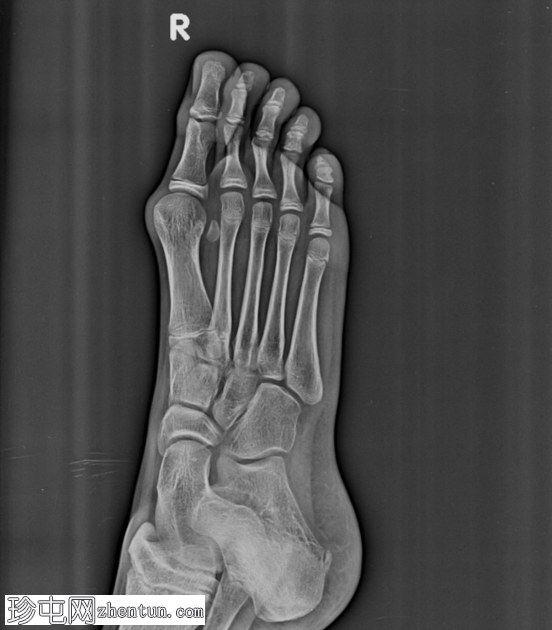

正位片

第一跖趾关节处拇趾(拇趾)向外侧偏斜。第一跖骨向内侧偏斜,导致拇外翻角增大。近节趾骨相对于第一跖骨头轻度向外侧半脱位。第一跖骨头内侧隆起,呈圆形。

未见急性骨折或脱位。其余可见的跖骨和趾骨排列正常。未见骨侵蚀或局灶性破坏性病变。